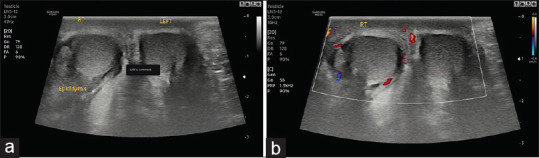

Acute Scrotal Pain - Role of Sonographic Evaluation in Solving Diagnostic Dilemma.